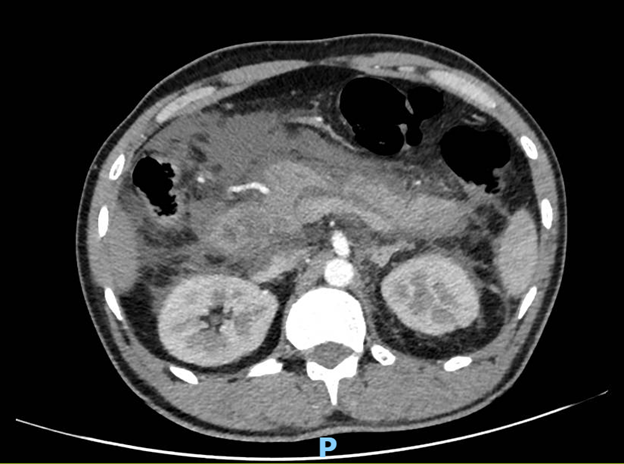

A 37-year-old male with a long-standing history of chronic smoking (15 pack-years) presented to the emergency department with the acute onset of excruciating, constant, epigastric pain that radiated sharply to his back. This severe pain began approximately 12 hours before presentation and was accompanied by multiple episodes of non-bloody, bilious vomiting and complete loss of appetite (anorexia). He is a chronic smoker (15 pack years) who denies any history of alcohol abuse, recent abdominal trauma, prior surgeries, or known history of gallstones. There has been no history of recent medication intake. Upon admission, he was diagnosed with moderate acute pancreatitis secondary to severe hypertriglyceridemia (serum triglyceride 2902 mg/dL), as supported by initial lab findings and imaging (modified CT scan severity index of 6/10) (Figure 1). He also exhibited signs of systemic inflammatory response syndrome (SIRS), including a fever of 38.5°C on arrival and a respiratory rate of 30 breaths/minute.

Figure 1: Contrast-enhanced CT abdomen